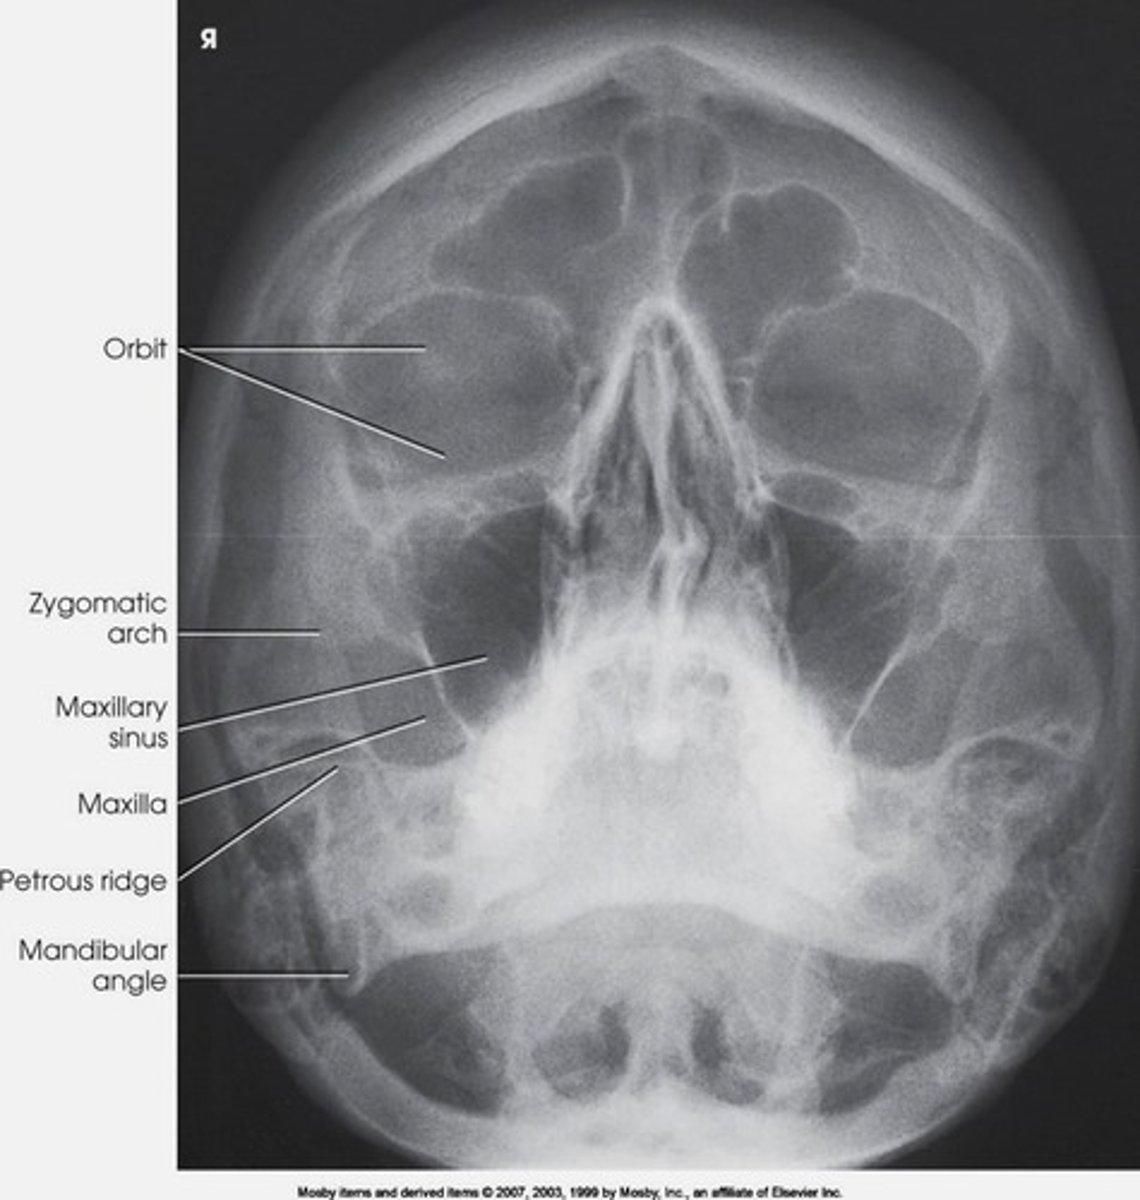

waters projection

shows maxillary sinuses

xray beam directed from behind head